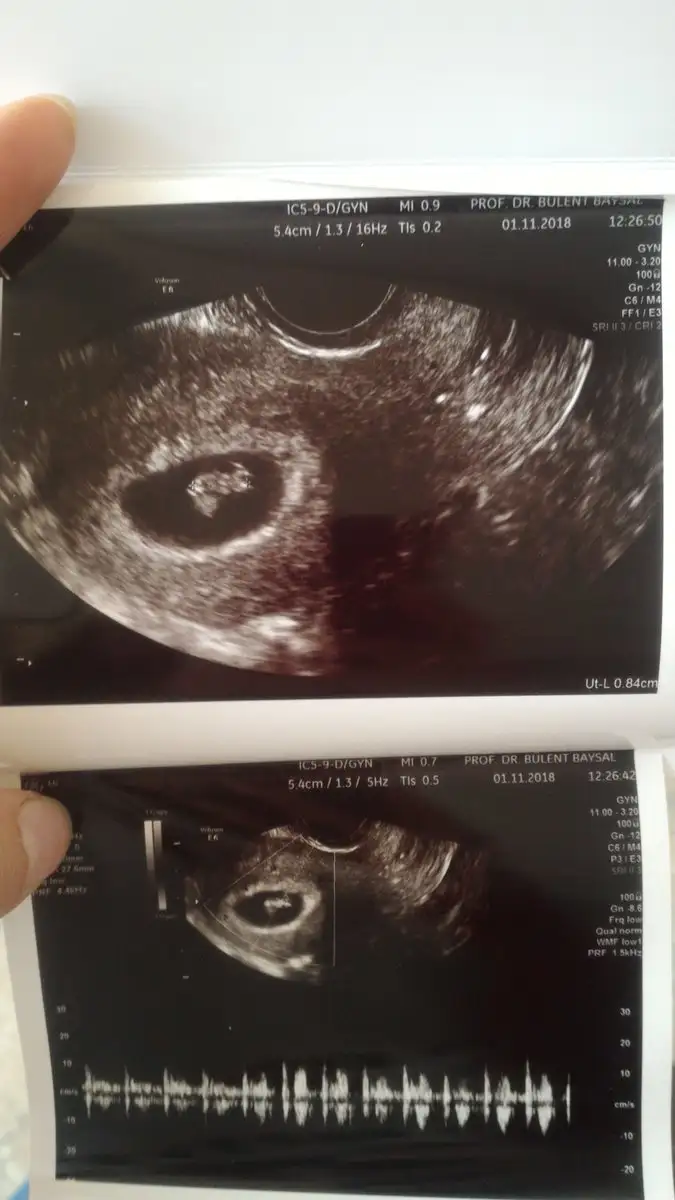

Ben de doktora gittim bugün. Daha büyük sanıyorduk sat ' a göre fakat henüz 5 hafta 4 günlükmüş. Henüz küçükmüşüz ama Yine de buyrun kesemiz, yolk sac'ımız ve hemen sağında keseye bitişik olan pek anlaşılmayan bir yapıdaki halimiz.kalp atışımızı da gördük elhamdülillah. Darısı gün bekleyenlerin başına... Eki Görüntüle 2202575